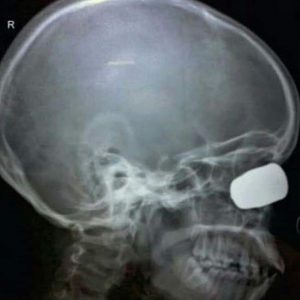

A radiografia mostrou fratura da parede orbital medial com penetração do corpo estranho por aproximadamente três centímetros dentro da órbita óssea.